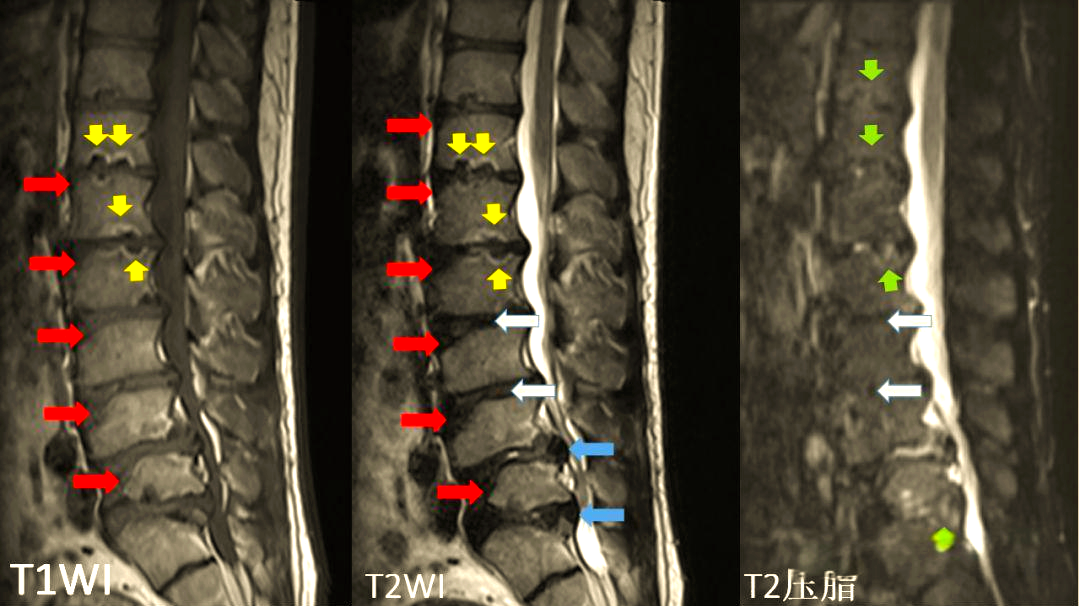

症状性胸腰段椎间盘突出为休门氏病的特殊表现

图片尺寸566x736

中间图符合腰型休门氏病标准.右图符合典型休门氏病标准.